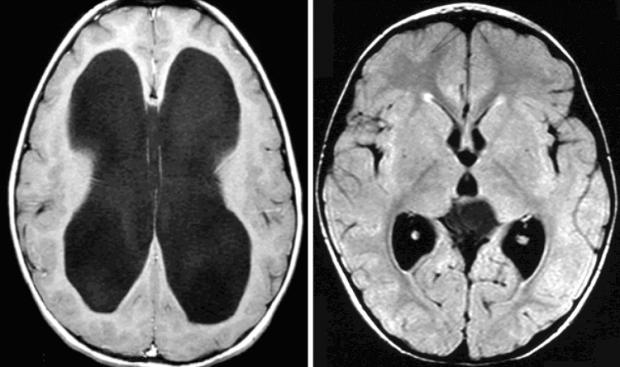

وبحسب منظمة الصحة العالمية، فإن استسقاء الرأس ذو الضغط الطبيعي اضطراب نادر يحدث نتيجة تراكم السائل الدماغي الشوكي CSF، داخل بطينات الدماغ، ما يؤدي إلى توسعها وزيادة الضغط على أنسجة المخ، رغم أن قياسات الضغط تكون غالبا ضمن الحدود الطبيعية، وهذا المرض يصيب بشكل أساسي كبار السن فوق سن الـ60 عاما، ويؤثر على الحركة، الذاكرة، والتحكم في المثانة.

تشخيص المرض يبدأ عادة بفحوصات تصويرية مثل الأشعة المقطعية أو الرنين المغناطيسي لرؤية توسع البطينات الدماغية، وقد يتم إجراء بزل قطني لتقييم الاستجابة بعد إزالة جزء من السائل النخاعي، والعلاج الأكثر شيوعًا هو إجراء جراحة لتركيب تحويلة «شنت» لتصريف السائل الزائد من الدماغ إلى جزء آخر من الجسم، ما يخفف الضغط ويحسن الأعراض لدى نسبة كبيرة من المرضى.